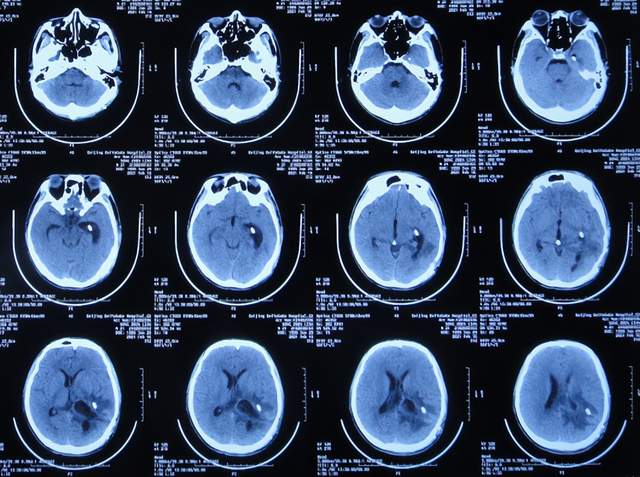

继续抗感染治疗1周的时间,仍精神差,食欲差,间断发热,期间3次查头颅影像(2021年1月29日头颅核磁增强(图-10)、2021年1月31日头颅CT(图-11)、2021年2月3日头颅核磁增强(图-12)均示颞角逐渐有扩张,有感染。

图-10:2021年1月29日头颅核磁增强

图-11:2021年1月31日头颅CT

图-12:2021年2月3日头颅核磁增强

2021年2月5日(脑膜瘤切除术后颅内感染3周)住入李小勇脑脊液科,入院时:精神差,食欲差,体温高(图-13);查头颅CT示脑瘤术后状态(图-14);(外院)2021年2月3日头颅核磁示有脑脓肿(图-12)。

图-13:2021年2月5日入院时

图-14:2021年2月5日头颅CT